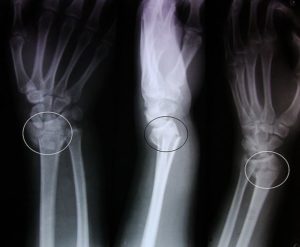

Лучевые методы диагностики являются «золотым стандартом» в диагностике переломов. Чаще всего в рутинной практике используется рентгенография конечности в двух проекциях.

Рентгеновский снимок покажет не только наличие перелома, но и его характер, наличие отломков, вид смещения и др. Эти данные играют ключевую роль в выборе лечебной тактики.

Иногда для диагностики сложных травм травматологи используют метод компьютерной томографии.

Для уточнения характера перелома и выбора дальнейшей тактики лечения используется рентгенография, в ряде случаев – компьютерная томография. Иногда требуется УЗИ кистевого сустава.

Как правило, для подтверждения перелома достаточно обычной рентгенографии.

Дополнительные диагностические методы – такие, как компьютерная томография (КТ) или магнитно-резонансная томография (МРТ) – необходимы только при сложных переломах для точной оценки сочетанных повреждений. Кроме того, подобные методы используются для предоперационного планирования и послеоперационного контроля.